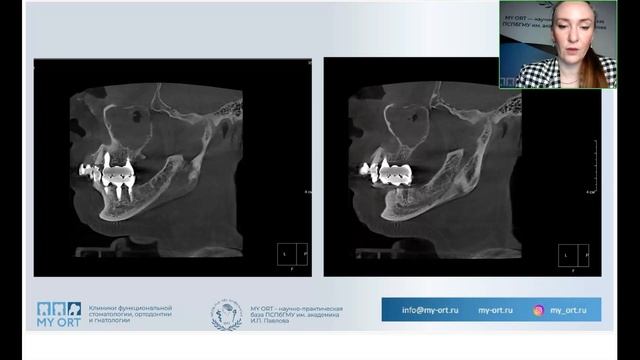

Кузьмин А. С. Минивинты. Хирургические основы. - видео